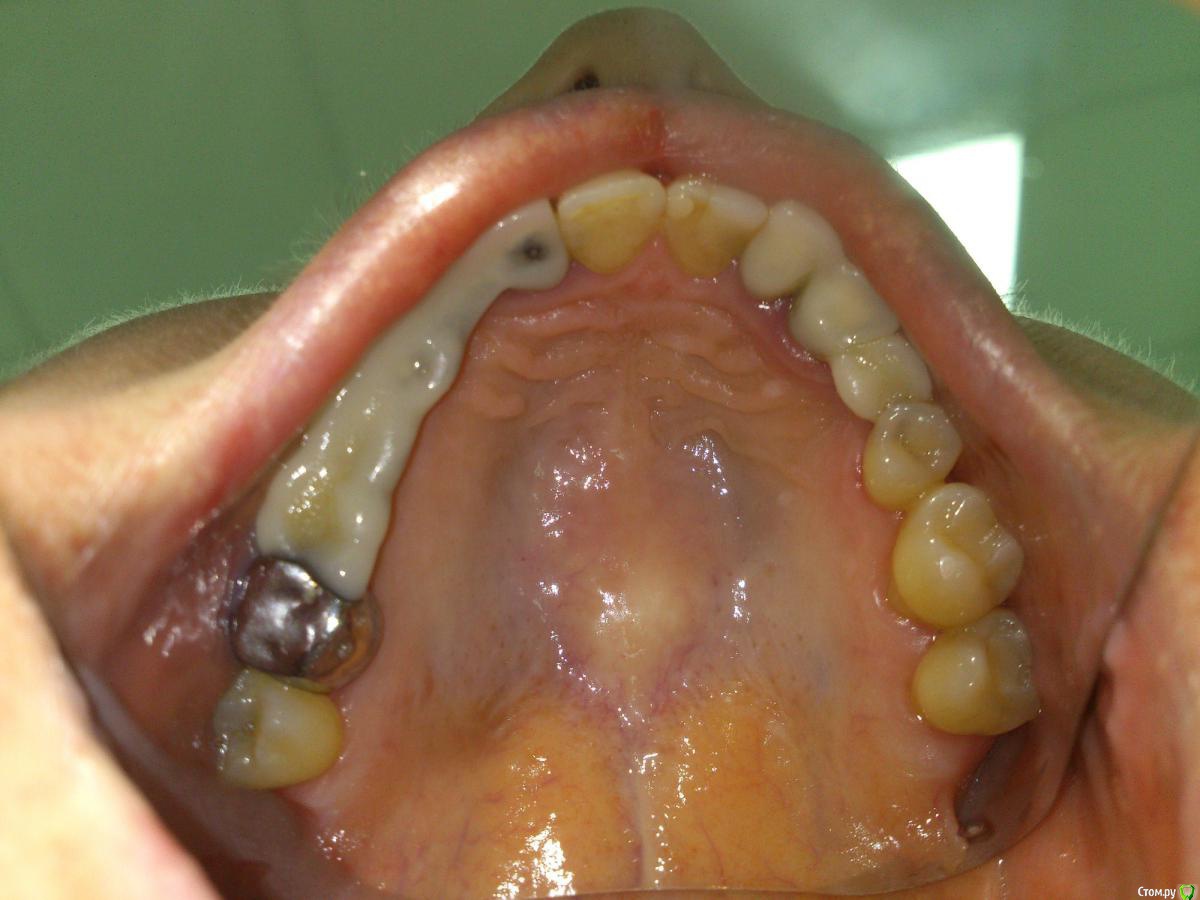

Карен Аванесов Опубликовано 1 декабря, 2015 Поделиться Опубликовано 1 декабря, 2015 Так и есть. эта самая практичная форма "все в одном". Ссылка на комментарий